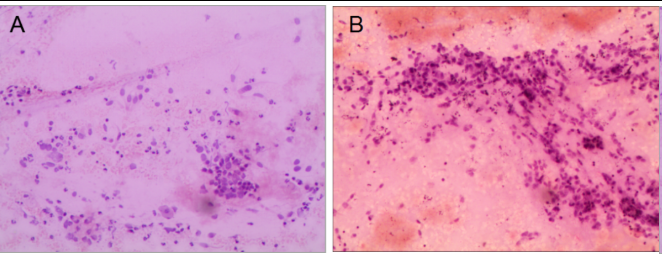

①2022-06-21(左肺下叶)纤支镜活检(脱落细胞学+病理):查见低分化癌,倾向小细胞癌(图1)。

图1 纤支镜活检病理结果(HE:200×) A为脱落细胞学检查;B为组织活检病理

②2022-07-20外院病理会诊-免疫组化:CK(+),P40(+),TTF-1(-),CD56(-),CgA(-),Syn(+/-),K1-67(+,30%),P63(+),NUT-1(+,75%细胞核颗粒状阳性),EMA(+),LCA(-),SMACA4(BRG+)。结合免疫组化结果,符合(左肺下叶)NUT癌。